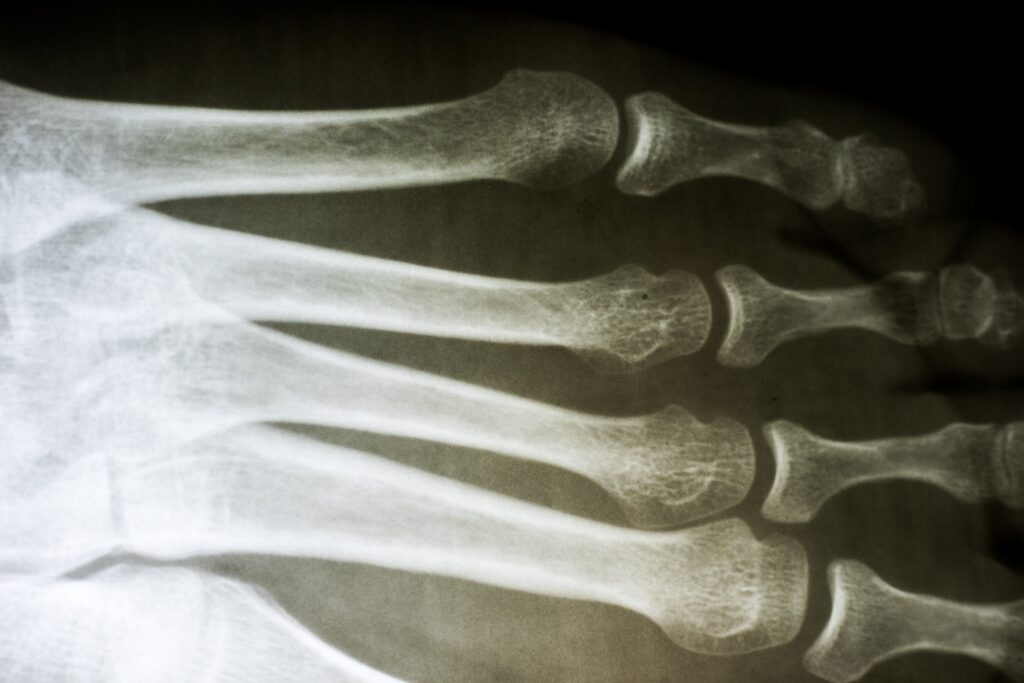

Just diagnosing your broken bone correctly is expensive. The procedure may include multiple X-Rays and MRIs, each costing hundreds or even thousands of dollars. Then, there are splints, casts, crutches, and wheelchairs that you might have to purchase. To heal properly, you may need surgeries and months of physical therapy. This is just the tip of the iceberg, as many broken bone injuries are accompanied by other symptoms and conditions.